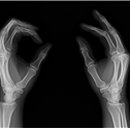

올바른 청구 G6501 수골 1매 × 1회 ※ 착오청구 예시 • G6502 수골 2매 × 1회 • G6501 수골 1매 × 2회 Q2... 올바른 청구 G6502 수골 2매 × 1회 ※ 착오청구 예시 • G6501 수골 1매 × 4회 • G6504 수골 4매 × 1회 • G6502...

올바른청구 G6502 수골 2 매 × 1 회 G6501 수골 1 매 × 2 회 G6501 수골 1 매 × 1 회 건강보험 요양급여비용... 1 매 5,400 6,170 G6502 나 . 2 매 7,650 8,730 G6503 다 . 3 매 8,990 10,260 G6504 라 . 4 매 10,330 11,780 G6505 마 . 5 매...

다-165 수골 Hand G6501 가. 1매 G6502 나. 2매 G6503 다. 3매 G6504 라. 4매 G6505 마. 5매 또는 그 이상 6. 다-166 수근골 Carpal Bone G6601 가. 1매 G6602 나. 2매 G6603 다. 3매 G6604 라. 4매 G6605 마. 5매 또는 그 이상

의료행위 건수를 부풀려 거짓청구 □□□의원의 경우, ‘손목의 상세불명 부분의 염좌 및 긴장(S6359)’ 등의 상병으로 내원한 수급권자 ○○○은 실제 수골 2매(G6502)를 촬영하였으나, 청구 시에는 수골 3매...